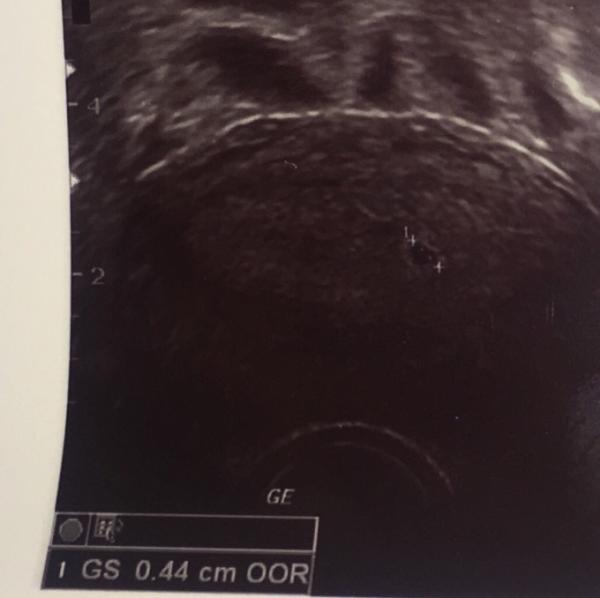

Hey:) war heute beim Frauenarzt und hab ein Ultraschallbild bekommen… Jetzt wollte ich fragen ob die Größe der Fruchthöhle (0,44cm) normal für die Zeit ist? Liebe Grüße Anna

Bild zu Normale Größe für 5+1? - Forum für Juli - Mamis

Hey ja das passt wir hatten am selben Tag 0,55 mm was zumindest meinen FA positiv überrascht hat da man bei vielen noch gar nichts sieht.